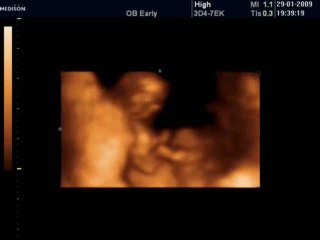

BCF Ultrason Görüntüsü - Hasvet Medikal